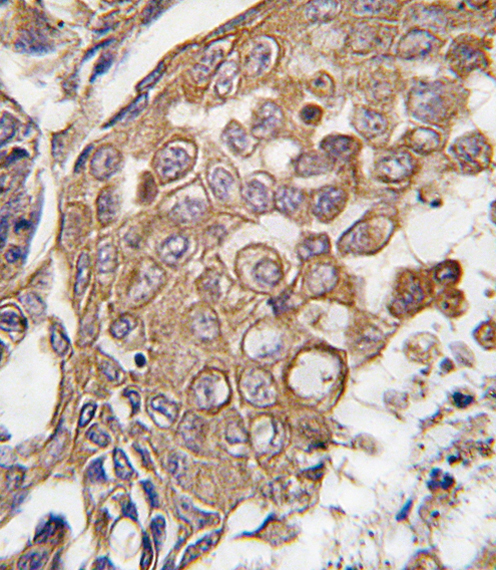

Product Image

- Formalin-fixed and paraffin-embedded human lung carcinoma tissue reacted with ALOX5AP antibody (Center), which was peroxidase-conjugated to the secondary antibody, followed by DAB staining. This data demonstrates the use of this antibody for immunohistochemistry; clinical relevance has not been evaluated.